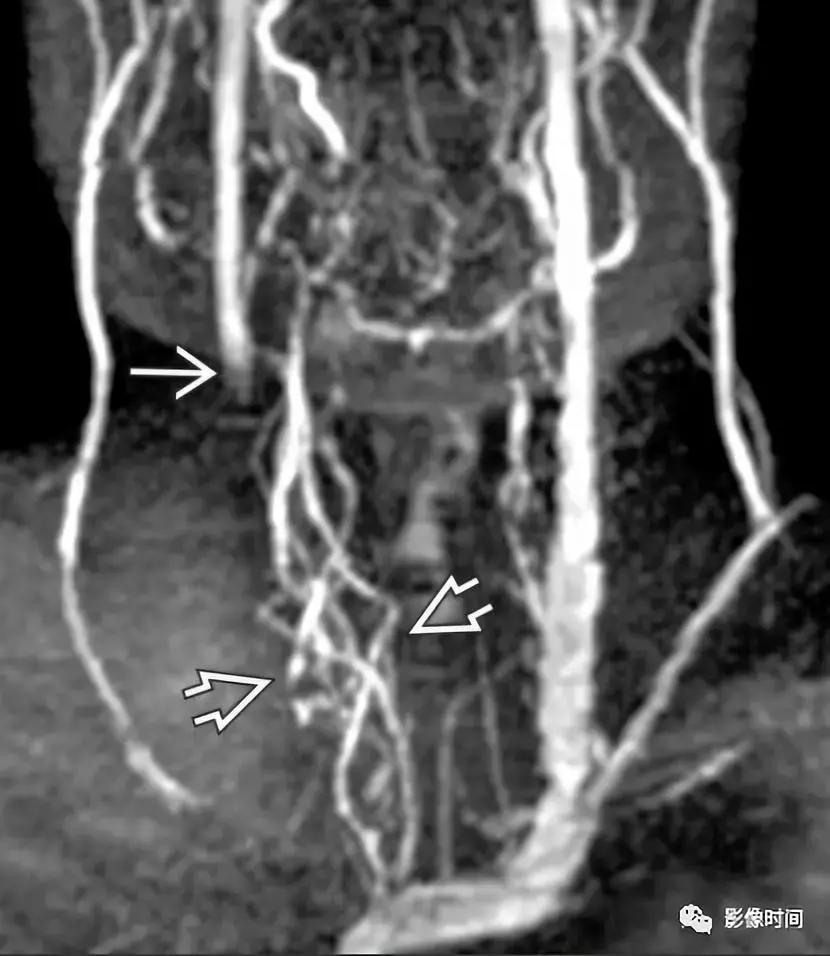

模式图显示纤维肌性发育不良的主要亚型:1 型表现为收缩和扩张的交替;2 型表现为管状狭窄,3 型表现为局灶性波纹+憩室。MRA 显示双侧颈内动脉「串珠」外观(箭头)。CTA 和 DSA 亦显示颈内动脉「串珠」外观。